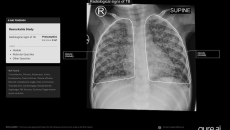

Its chest X-ray analysis AI tool is the first to receive Europe's clearance for use in children aged 0-3.

The deep multi-task learning AI analyses X-ray images of premature babies to identify intestinal perforation and its location.